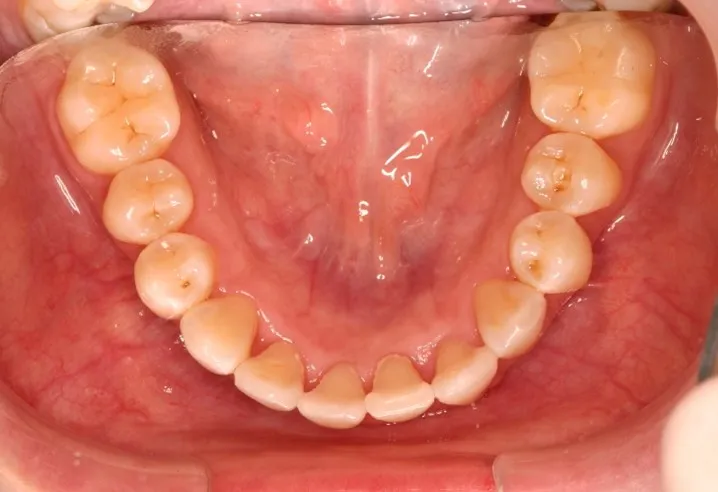

Invisalign Before and After Photos